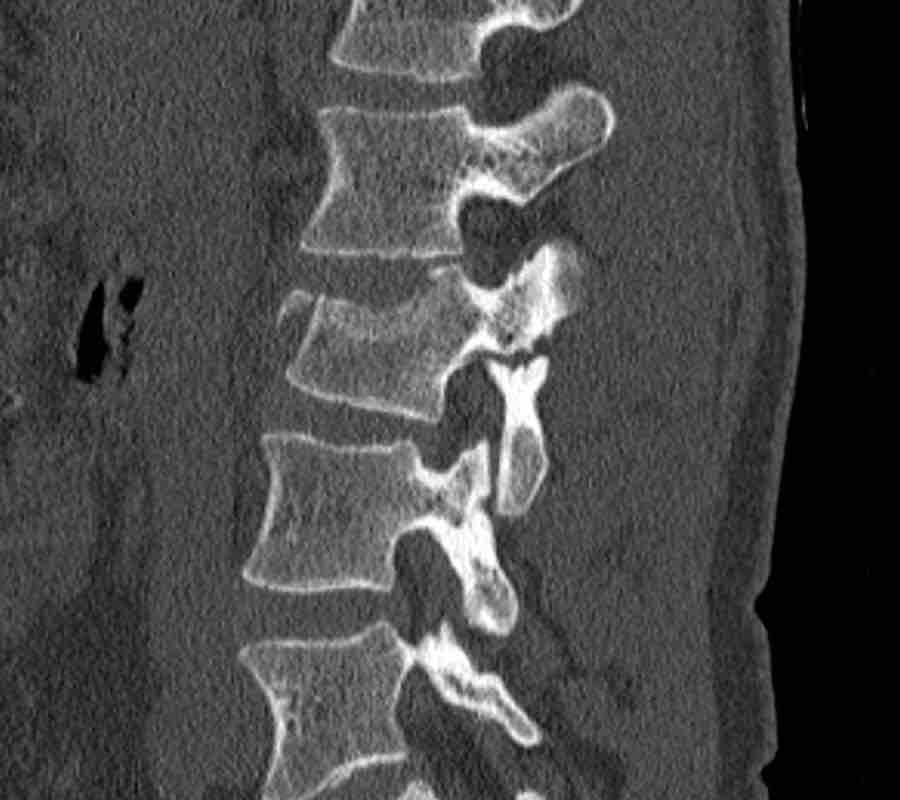

This is a difficult case with injuries at many levels.

What is the most severe level for classification.

Then continue with the second stack below for classification of other levels.

Findings

- The most severe level is L4/5 with dislocation (dotted lines)

- Facet fractures at L4 (arrows).

- A4 burst fracture (circle).

Conclusion:

Injury type C + A4 at L4/5.

Continue with the next stack of images to classify level L2…